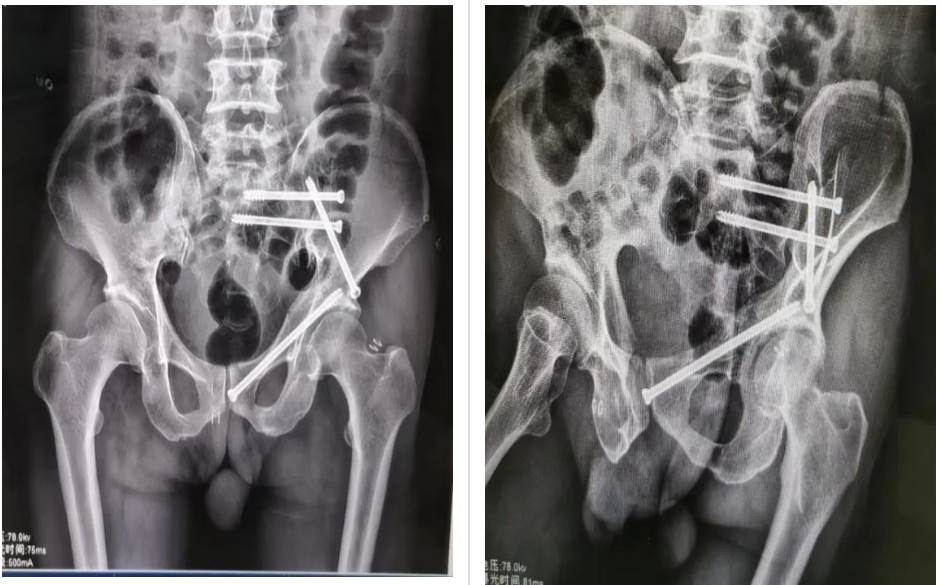

術(shù)中,在醫(yī)院手術(shù)室的大力支持下,主刀醫(yī)生冷明昊主任首先將定位追蹤器安置在患者髂棘合適位置上,再結(jié)合CT透視所得將患者骨盆影像資料導(dǎo)入手術(shù)機(jī)器人中,通過機(jī)器人自動(dòng)化算法將影像圖片與骨盆實(shí)體情況進(jìn)行精準(zhǔn)配對(duì),并在顯示器上規(guī)劃好骶髂螺釘、前柱螺釘位置、長度以及角度,隨后準(zhǔn)確無誤地將骶髂螺釘、前柱螺釘植入患者體內(nèi)。手術(shù)全程通過機(jī)器人監(jiān)視下調(diào)整角度,快速定位、精準(zhǔn)植入、切口僅用1cm,術(shù)中出血量約10ml,手術(shù)安全順利結(jié)束。術(shù)后,患者恢復(fù)良好,目前可在床上自行翻身、端坐等活動(dòng)。

據(jù)介紹,骨科手術(shù)機(jī)器人可將虛擬與現(xiàn)實(shí)相結(jié)合,在機(jī)器人實(shí)時(shí)顯示下完成骨折復(fù)位、智能規(guī)劃、輔助置釘?shù)目梢暬僮,機(jī)器人定位導(dǎo)航精準(zhǔn)度可達(dá)“毫米級(jí)”,使手術(shù)更簡潔化、精準(zhǔn)化、規(guī)范化,其優(yōu)勢(shì)在于能夠減少透視次數(shù)、減小輻射危害,同時(shí)也降低人為誤差,治療更加安全可靠。